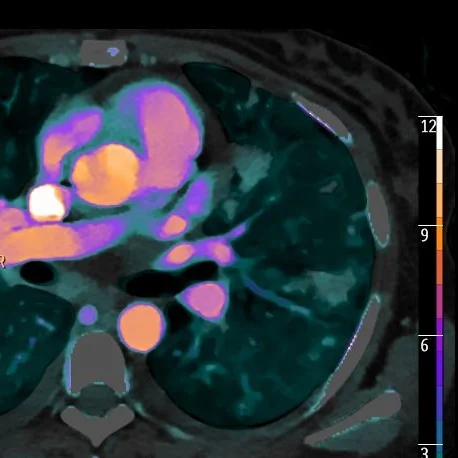

Adrenal "incidentaloma"

Gopal Punjabi

March 15, 2018